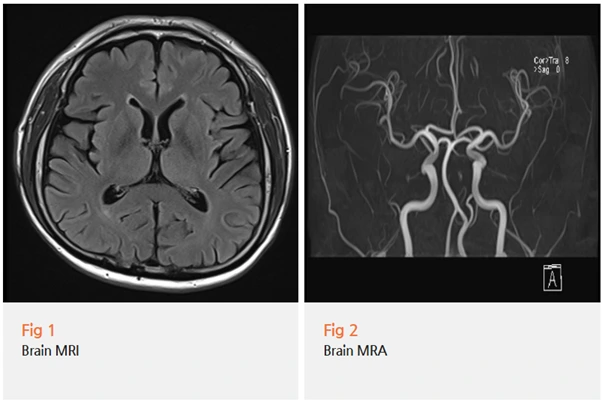

뇌신경 쪽 문제를 먼저 확인해야 한다고 판단했어요.

안면부 감각 이상과 귀 통증은 중추신경계 병변에서도 나타날 수 있기 때문에,

당일 뇌 MRI와 MRA 검사를 먼저 진행했습니다.

결과는 다행히 뇌 자체에는 문제가 없었어요.